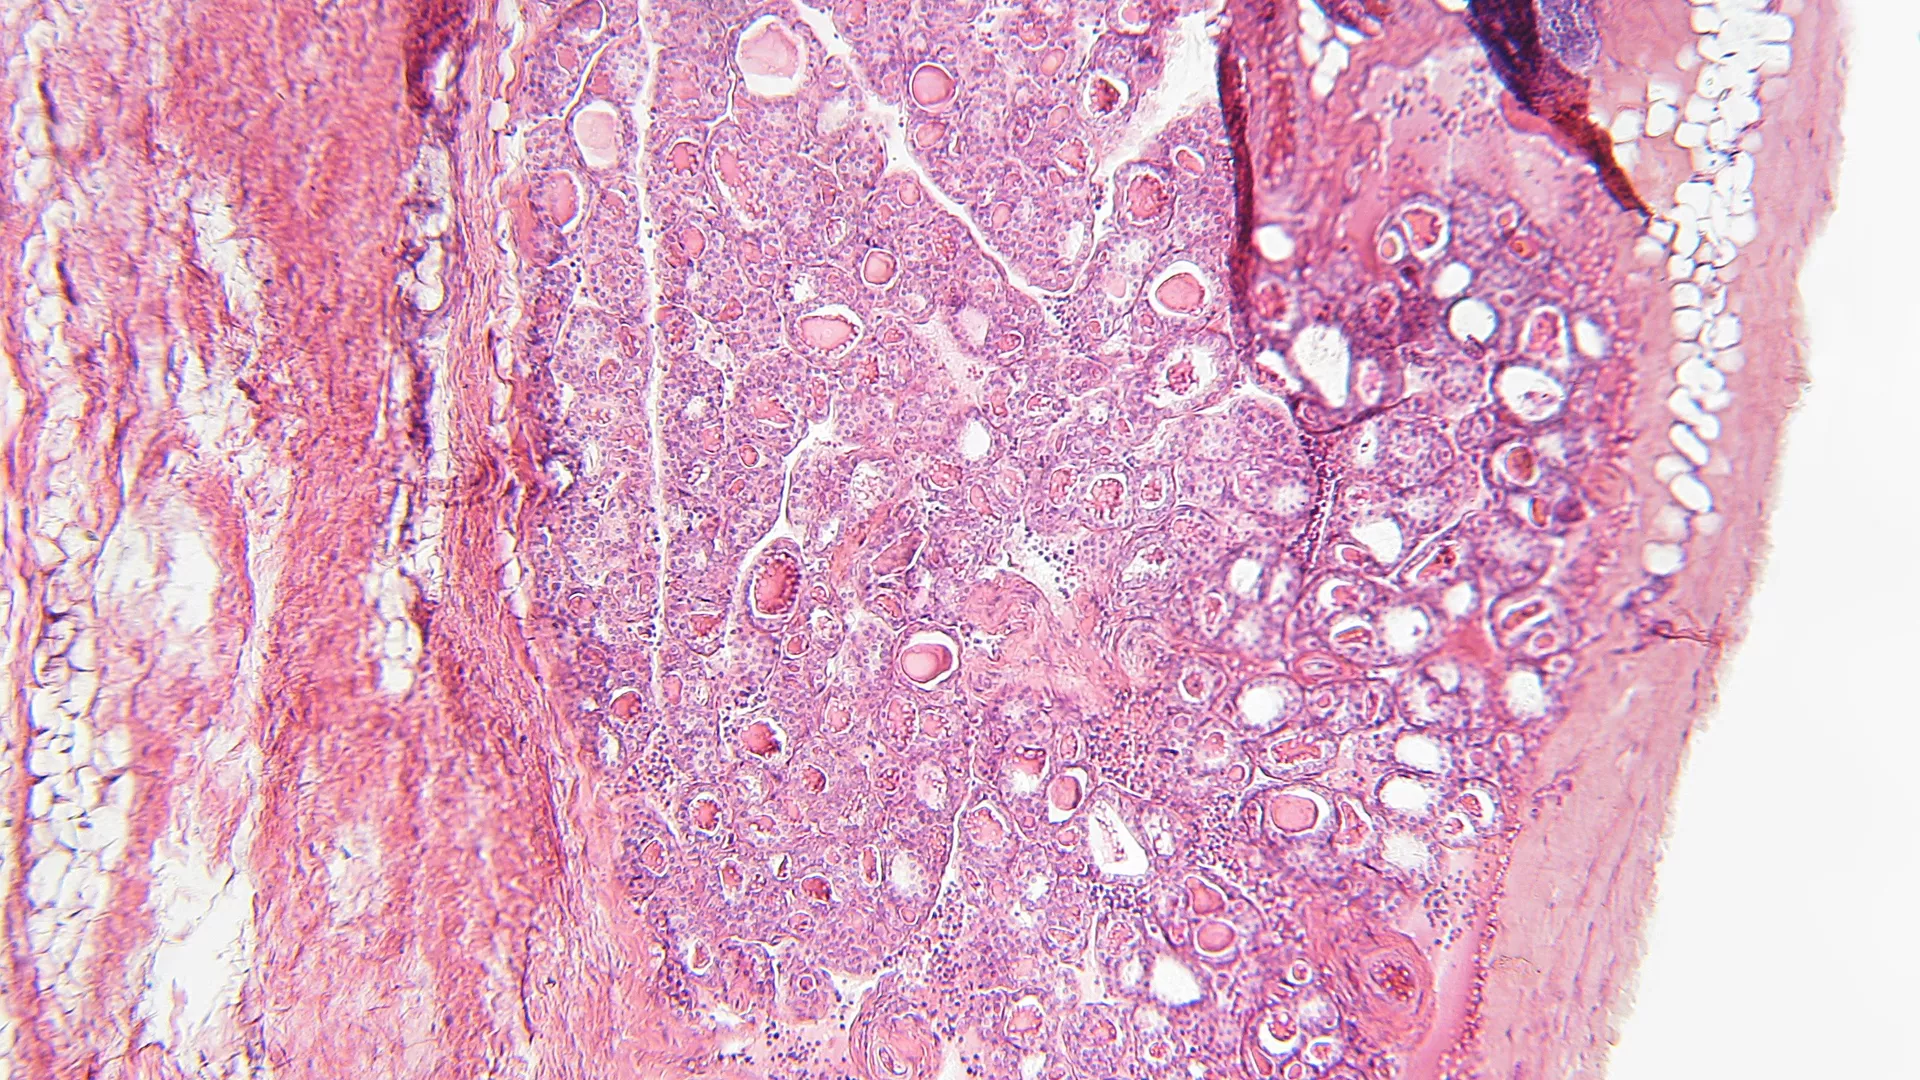

The most prevalent autoimmune diseases affecting endocrine glands are hypothyroidism (Hashimoto’s disease) and hyperthyroidism (Graves’ disease). Both of these thyroid diseases cause chronic inflammation, and the former one is a known factor associated with an increased risk of thyroid cancers. A rare case of a thyroid collision tumor was detected by Zhang et al. in a 64-year-old patient. This rare coexistence of primary thyroid mucosa-associated lymphoid tissue (MALT) lymphoma and papillary thyroid cancer was treated with a total thyroidectomy along with lymphadenectomy of the central compartment without any further signs of metastasis or tumor recurrence. Hashimoto’s thyroiditis is associated with both, MALT lymphoma and PTC. However, MALT lymphoma is less prevalent in the thyroid and more frequent in the stomach, often being caused by Helicobacter pylori-induced chronic inflammation.